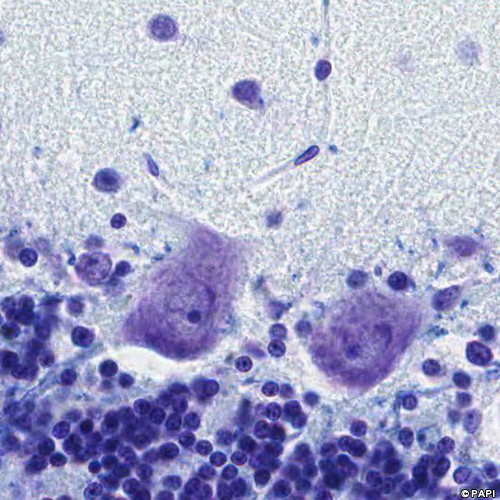

Red arrows indicate the Purkinje cells. Black arrows indicate the nuclei of the Bergmann glia which is the astrocyte in the Purkinje cell layer. Yellow arrows points the basket cell in the molecular layer.

The Purkinje cell (a yellow arrow) is surrounded by the axon (white arrows) of the basket cell (a blue arrow).